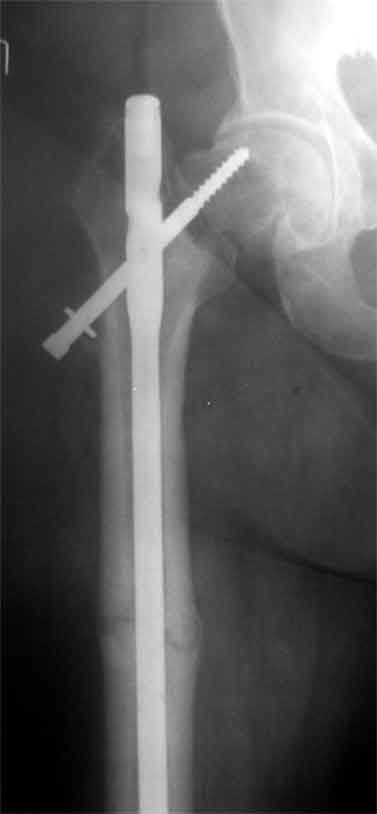

Доброго время суток, коллеги. Обратилась на консультацию пациентка 52 лет. травма и первичный остеосинтез перелома бедра около года назад, далее был обнаружен перелом шейки бедра (возможно ятрогенный), реостеосинтез реконструкционным гвоздем 8 месяцев назад. Конченость не опорна. В больнице, где выполнялись эти вмешательства предложили выполнить THR с длинной ножкой. Возможно ли в такой ситуации добиться сращения шейки при помощи каких-либо остеотомий?

На мой взгляд дистальный перелом срощен, а состояние тазобедренного сустава и молодой возраст пациентки позволяют произвести вальгизирующую остеотомию проксимального бедра. В случае, если нет сращения дистального перелома можно фиксировать длинным DHS; Если есть сращение- обычным DHS.

Применение одного импланта для лечения ипсилатеральных переломов резко ограничено из-за риска осложнениий, связанных с применением неадекватной фиксации. По литературным данным, осложнения после применения зарекламированных реконструктивных гвоздей для лечения ипсилатеральных переломов доходили до 56%.

Несостоятельность фиксации шейки не давала возможности срастись перелому, потому что запланированнная динамическая нагрузка в большинстве случаев прекращалалась из-за вторичного варусного смещения шейки.

Сегодня применяемые новые реконструктивные гвозди Intertan и Gamma 3, которые имеют возможности создания угловую стабильность за счет блокировки гвоздя и шурупа в проксимальном отделе бедра, пока

недостаточно изучены для восстановительных операции на шейке.

В идеале свежие ипсилатеральные переломы надо лечит отдельно каждый:

шейку паралельними шурупами, бедро ретроградным методом. При латеральных переломах шейки 130 градусный DHS с ретроградным гвоздем.

Тогда импланты, не мешая друг другу, создадут компрессию на бедре и скольжение в шейке.

В данном случае навряд ли можно ожидать образования сращения на бедре и еще имеется укорочение засчет варуса.

Для предоперационной планировки необходимо сравнительные ренгенограммы с другой стороны, которая точно укажет истинную длину конечности. КТ

поможет установит сращение на шейке и бедре. Восстановление длины можно сделать за счет вальгусной остеотомии оригинальным методом Blade Plate. На бедро шт ифт ретроградно или пластина, кому что нравится. На мой взгляд, еще имеется шанс спасти головку остеотомией.